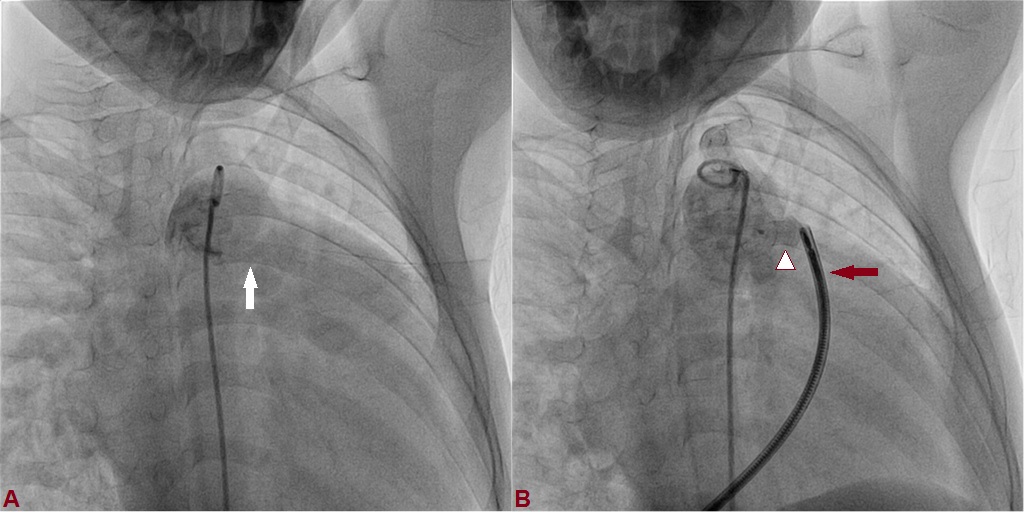

Importance of pin-vise of duct occluder during percutaneous closure of Patent Ductus Arteriosus (PDA)

Santosh Sinha*

Patent ductus arteriosus (PDA), a persistent left to right shunt at great arterial level, accounts up to 10% of all congenital heart disease. Here, we report a case of a 6-month old baby with large PDA (5mm) whose percutaneous closure was planned...